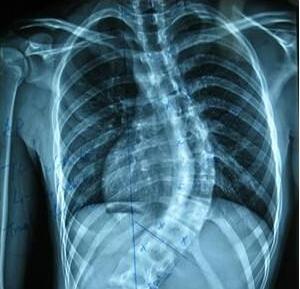

• X光检验强直病是不是误诊率很高?

强直性脊柱炎这种疾病对于小儿的健康是有很大的影响的一种疾病, ...